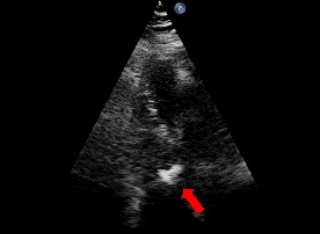

释放后评估

封堵器形态良好,基本无残余分流

本例患者于外院体检时发现心脏异常,升主动脉造影初步提示破口约8mm。由于患者抵抗力较低,如植入镍钛合金封堵器,术后需终身预防感染性心内膜炎,因此外院曾建议行外科手术修补。为进一步明确破口情况,术前团队对其进行了详尽的超声及造影评估,确认破口直径约为5mm,血流通向右房。考虑到破口位置靠近瓣膜,且可降解封堵器能够实现生理性修复,术后不留异物,无需终身预防感染性心内膜炎,本次手术最终选用ABFDQ-II 10全降解封堵器进行封堵。该封堵器材料柔韧,植入后可自适应周围结构及组织运动,不易影响或磨损瓣膜功能。术中释放后封堵器形态稳定,瓣上造影显示基本无残余分流,主动脉瓣启闭正常,手术取得圆满成功。术后1天超声复查提示瓦氏窦瘤封堵效果良好,封堵器位置及功能正常,患者恢复顺利,已康复出院。